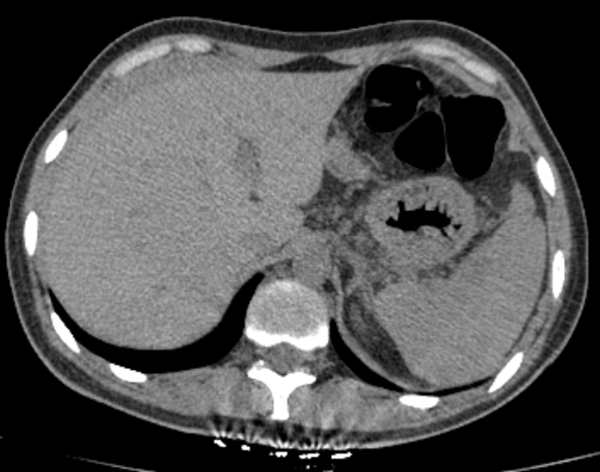

检查结果回报,血常规提示血色素94g/L轻度下降,急诊B超显示肝周可见低密度影。立即联系普外科,用平车将患者送去行腹部CT检查,放射科报告危急值:发现脾脏密度不均,腹腔积液,考虑脾破裂。普外科立即给患者办理入院手续,郭春海任杰医生加班为患者行急诊腹腔镜探查手术,术中见腹盆腔内大量积血及血凝块,脾脏下极破裂,行脾修补术及自体血回输。术后患者病情稳定,顺利出院。

▲腹部CT提示脾脏密度不均,肝周积液,考虑脾破裂